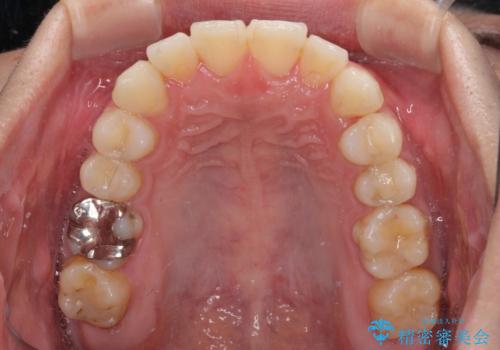

- 右下奥歯の虫歯がしみて痛いとのことで来院された患者様です。

神経近くにまで及ぶ大きな虫歯でしたが、速やかに処置を行い、痛みは即日解消されました。

虫歯が大きかったため、クラウンによる補綴治療が必要になる旨をお伝えしたところ、矯正治療にも興味があるとのことでした。

短期間で手間のかからない方法がご希望でしたので、ワイヤー装置による矯正治療を行うこととし、矯正治療後に右奥2歯をセラミッククラウンにて補綴することとしました。